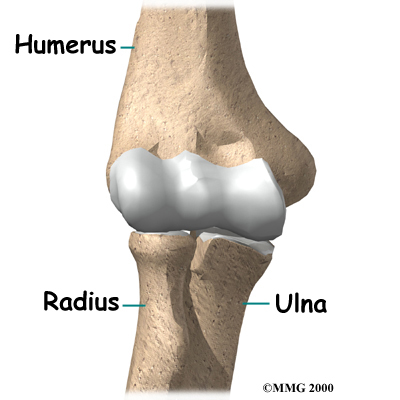

The elbow joint is made up of : the humerus bone of the upper arm, and the ulna and radius bones of the forearm.

The ulna and the humerus meet at the elbow and form a hinge. This hinge allows the arm to straighten and bend. The large triceps muscle in the back of the arm attaches to the point of the ulna (the olecranon). When this muscle contracts, it straightens out the elbow. The biceps muscles in the front of the arm contracts to bend the elbow.

Inside the elbow joint, the bones are covered with articular cartilage. Articular cartilage is a slick, smooth material. It protects the bone ends from friction when they rub together as the elbow moves. Articular cartilage is soft enough to act as a shock absorber. It is also tough enough to last a lifetime, if it is not injured.

The connection of the radius to the humerus allows rotation of the forearm. The upper end of the radius is round. This round end turns against the ulna and the humerus as the forearm and hand turn from palm down (pronation) to palm up (supination).